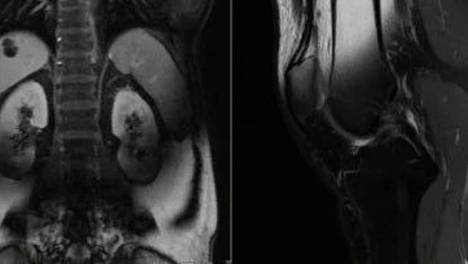

近日,美国一名61岁的男子陪同亲友就医时,疑似因佩戴金属项链🥳违规闯入扫描室,当场被强力磁场吸入机器,身受重伤,第二天就不🤯治身亡了。警方表示,该男子并非接受检查的病患,而是陪同1名亲😡友接受医疗扫描。医生推测,该…